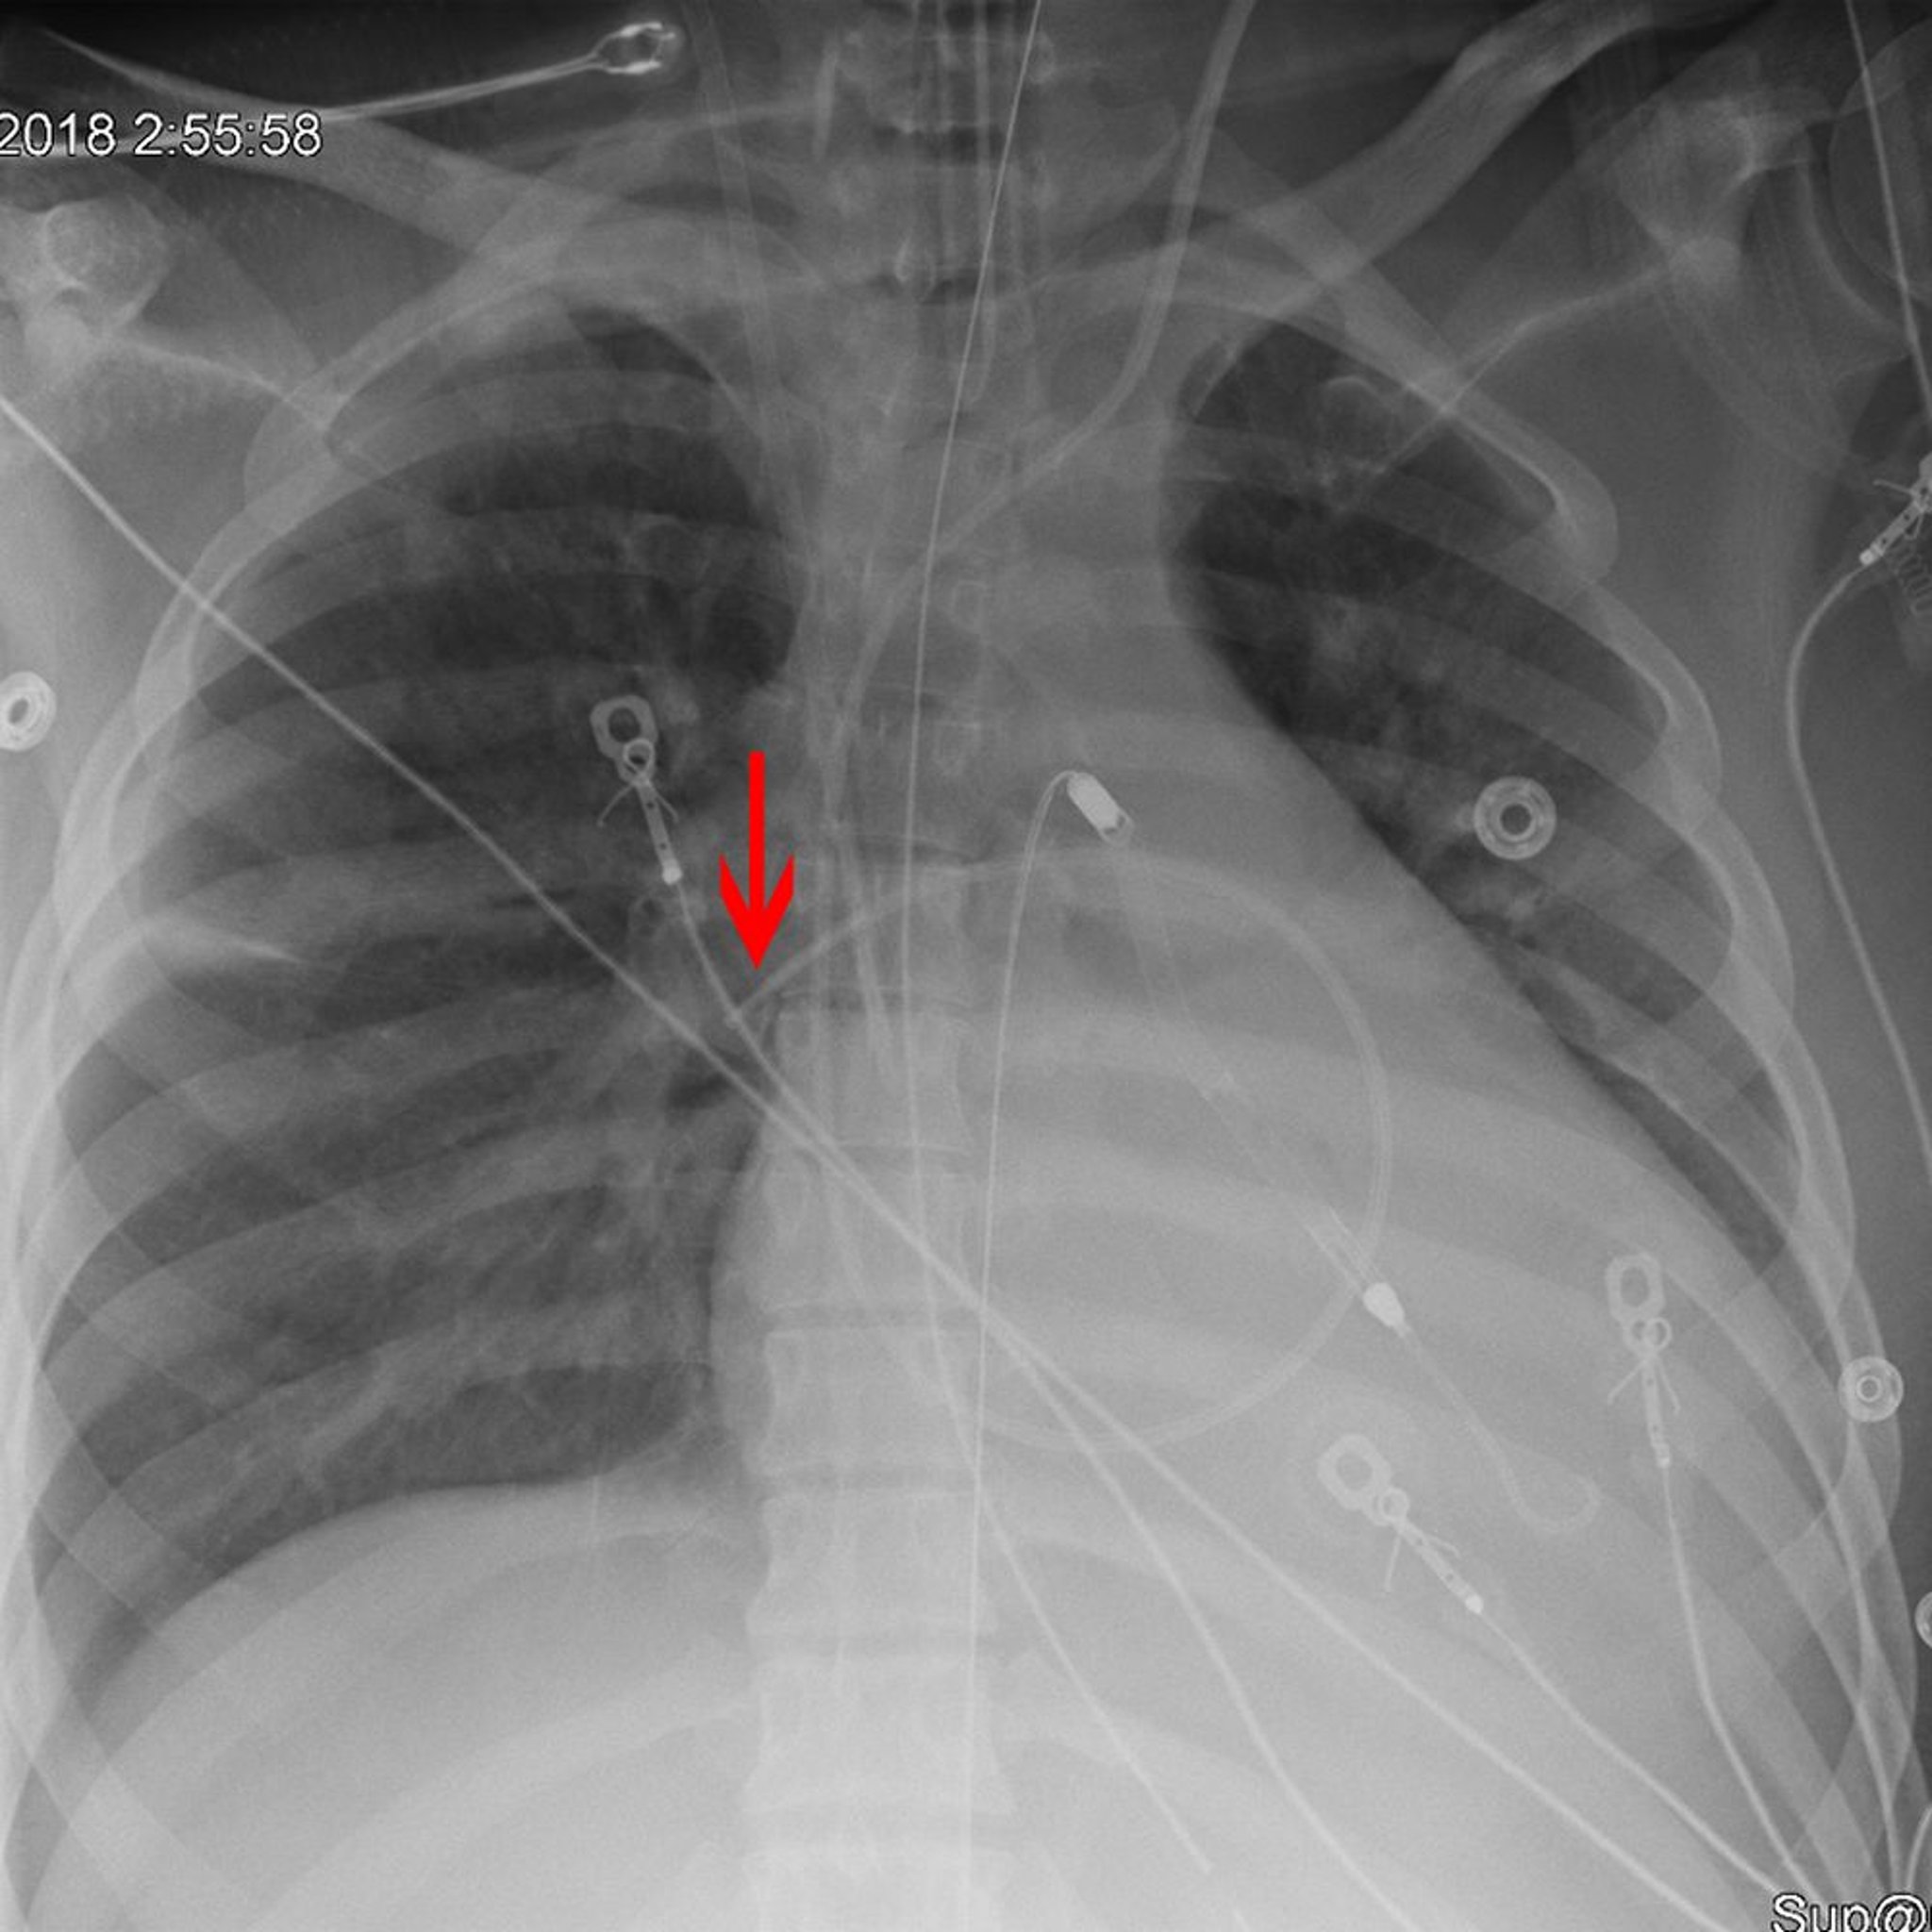

Radiografía que muestra la colocación correcta de un catéter de Swan Ganz

La flecha señala la punta de un catéter de Swan Ganz (arteria pulmonar) (colocado apropiadamente en la arteria pulmonar derecha).